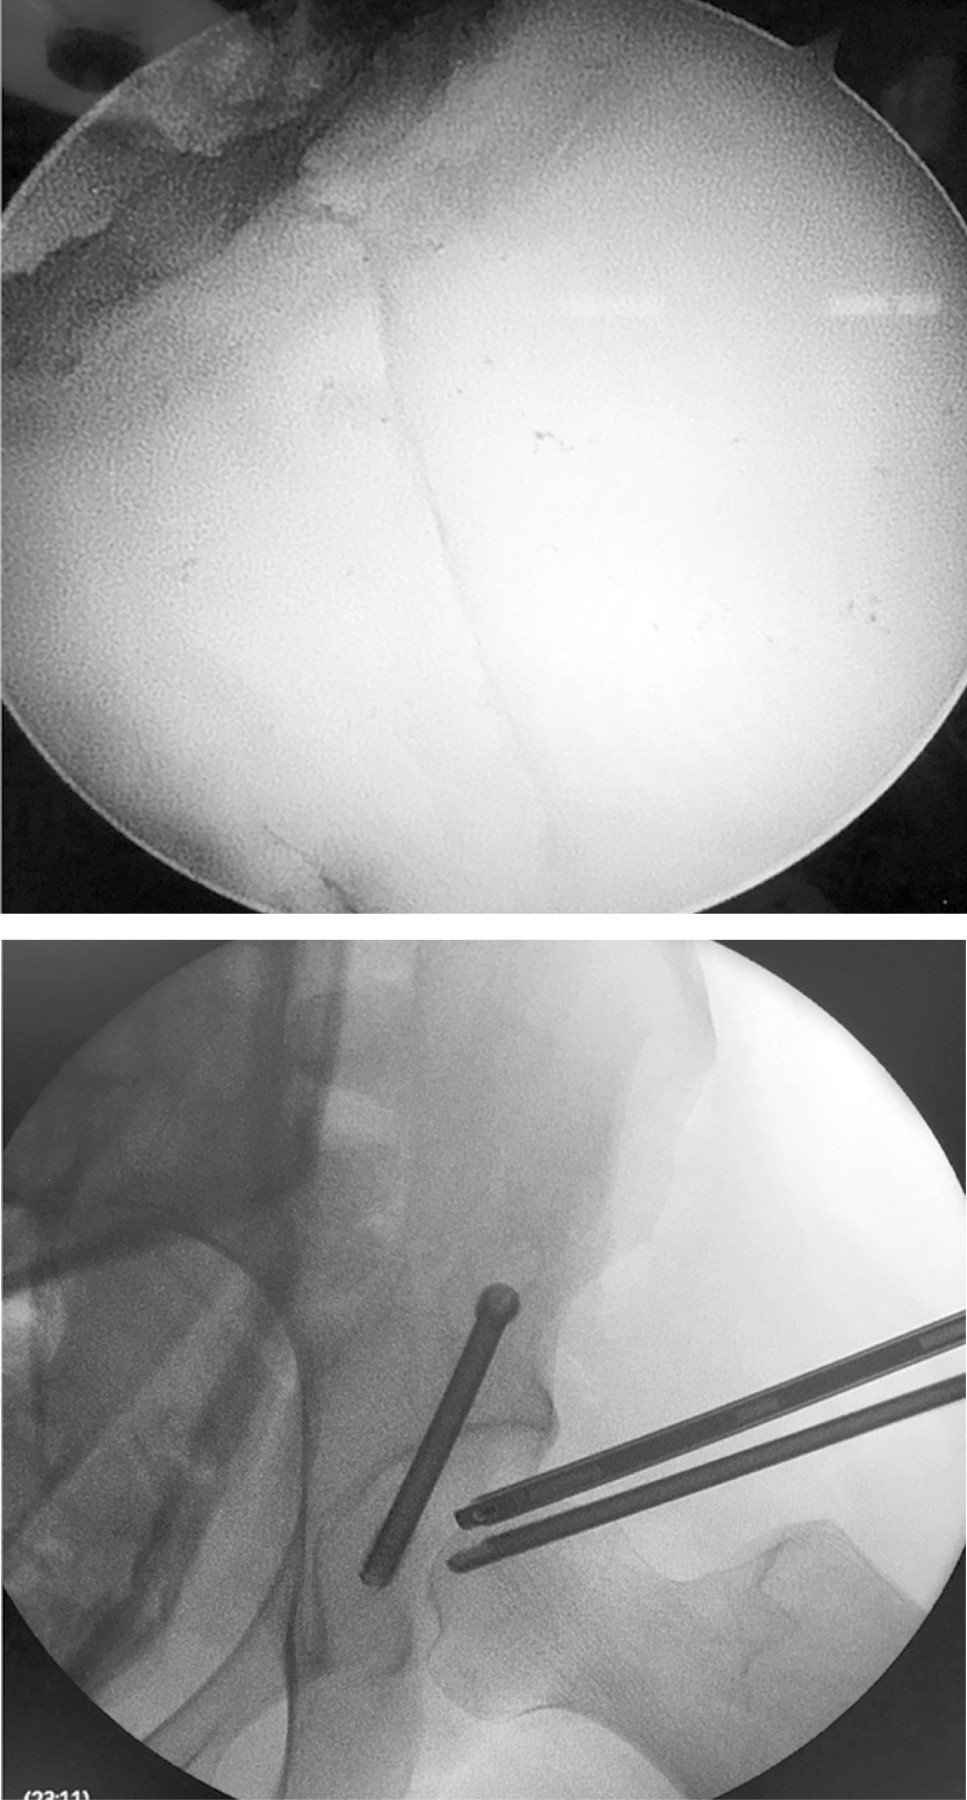

Al realizar la tracción de miembro pélvico izquierdo se logró la subluxación con apertura del espacio articular coxofemoral necesario para la introducción del material artroscópico. Por el portal anterolateral se introdujo el lente de 70 grados para visualización intraarticular. Se localizó con visión intraarticular el portal anterior estándar para introducción de material de trabajo. En la exploración articular se observó hemartrosis con sinovitis inflamatoria, se realizó lavado intraarticular y hemostasia, se extrajeron fragmentos libres de cartílago con punta de rasurador. Se localizó lesión traumática de labrum en región posterior acetabular, la cual se estabilizó con radiofrecuencia, se ubicó el trazo de fractura acetabular en columna posterior longitudinal simple con separación de 4 mm (Figura 4). Se realizó abordaje de 4 cm en primera ventana de Judet y se disecó por planos hasta localizar con guía canulada el punto de entrada para la colocación de tornillo de compresión, asistido por fluoroscopía de 7.0 mm por 85 mm y bajo visión directa intraarticular para observar el cierre del trazo de fractura con congruencia articular satisfactoria (Figura 5). Finalmente se procedió a la extracción de instrumental artroscópico y cierre de heridas por planos.

Figura 4